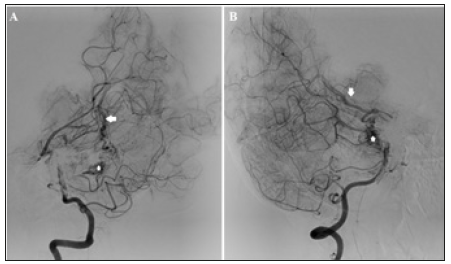

Figure 3:(A) Lateral (B) Oblique views of a super selective venography delineating the targeted nidal compartment of the AVM. (C&D) Lateral and oblique non-subtracted images “the same as in A&B” after final Onyx injection. The targeted compartment was totally occluded, with extension of Onyx toward small part of another compartment

Injection of Onyx® 18 was started by making a plug to occlude the vein to allow progress of Onyx into the nidus. The Onyx partially diffused also toward the other compartment. Finally, a sufficient occlusion of the nidus is reached. The other draining vein is left to act as a safety valve and drains the remaining part of the nidus (Figure 3).